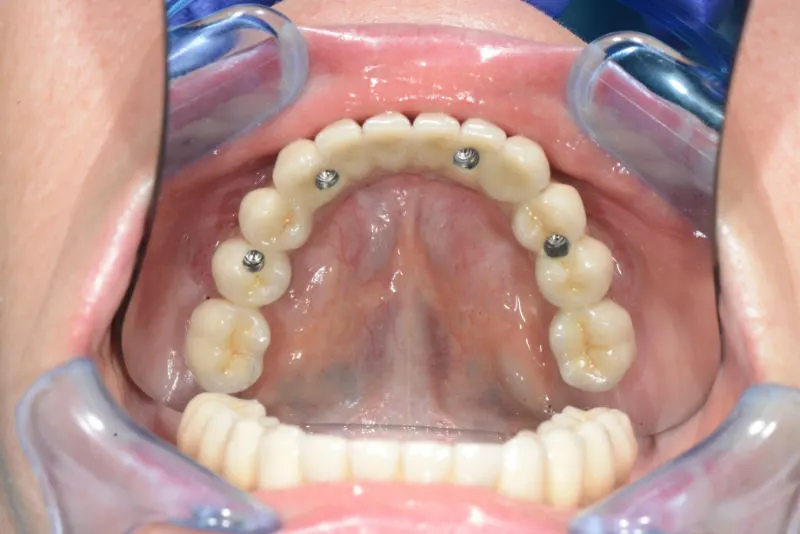

- Поставят се четири импланта в костта.

- Към тях се свързват специални мулти-юнит абатмънти.

- Към мулти юнит абатмънтите се свързва конструкцията.

- След 6 месеца временният мост се сменя с постоянен такъв от цирконий от 12 зъба, изработен по най-съвременна CAD/CAM технология в нашата собствена зъботехнична лаборатория.